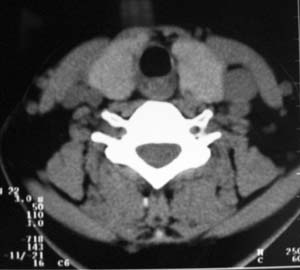

以下是引用zsl6918在2007-8-27 14:40:00的发言:[br]双侧甲状腺多发性低密度占位,边界清晰,密度欠均匀,尤以左侧明显,与周围组织分解清,考虑多发性腺瘤可能性大,不除外结节性甲状腺肿

以下是引用liaizhi在2007-8-27 15:20:00的发言:[br]双侧甲状腺散在多个囊性第密度影,左侧最大一个病灶与正常甲状腺分界尚可,气管受压稍右移。考虑甲状腺瘤的可能性大。

以下是引用zsl6918在2007-8-27 14:40:00的发言:[br]双侧甲状腺多发性低密度占位,边界清晰,密度欠均匀,尤以左侧明显,与周围组织分解清,考虑多发性腺瘤可能性大